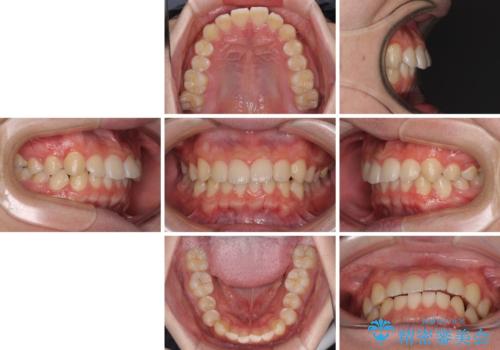

【モニター】斜めに突き出した前歯をインビザラインで改善

- 前方に傾斜した前歯を気にして来院された患者様です。

強く食いしばってしまう癖があり、下顎前歯に押し出されて上顎前歯が前方へ斜めに突き出している状態でした。

IPR(歯と歯の間を削る)を多用して、インビザラインにて矯正治療を行うこととしました。

口元を引っ込めるためのゴムかけを頑張っていただき、満足のいく上顎前歯の傾斜へ改善することができました。